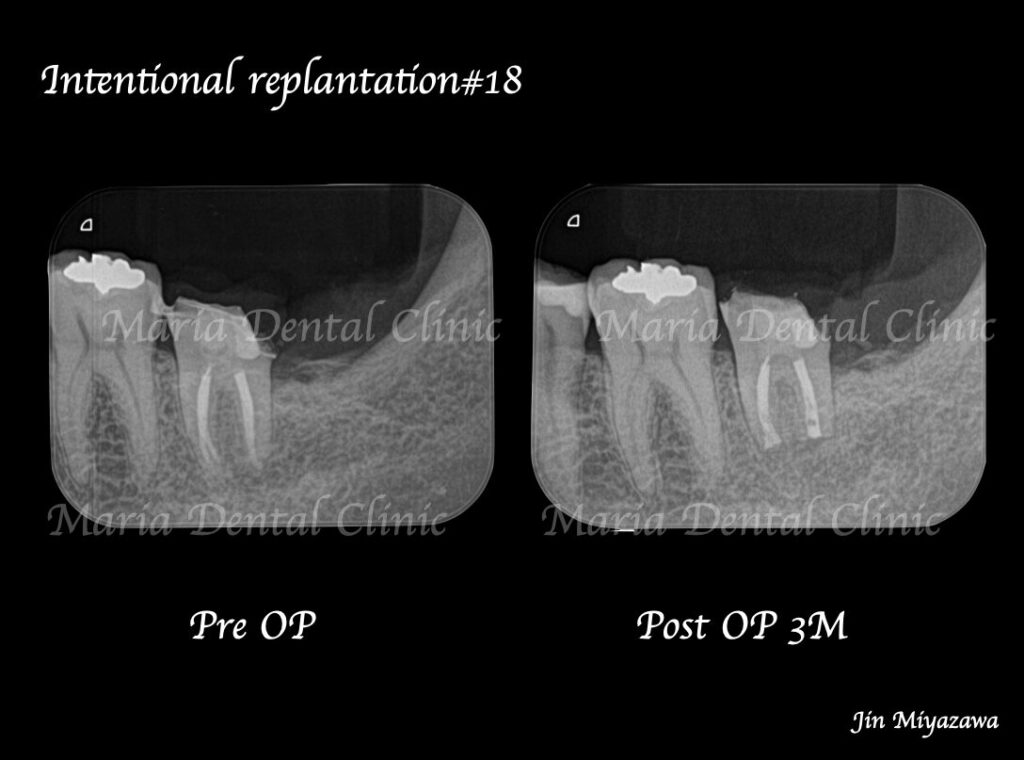

違和感や痛みは術後1ヶ月程で消失し、3ヶ月後には術直後に見られていた左下7番根尖部に確認できた透過像も消失し、順調に骨が作られていることが確認できます。